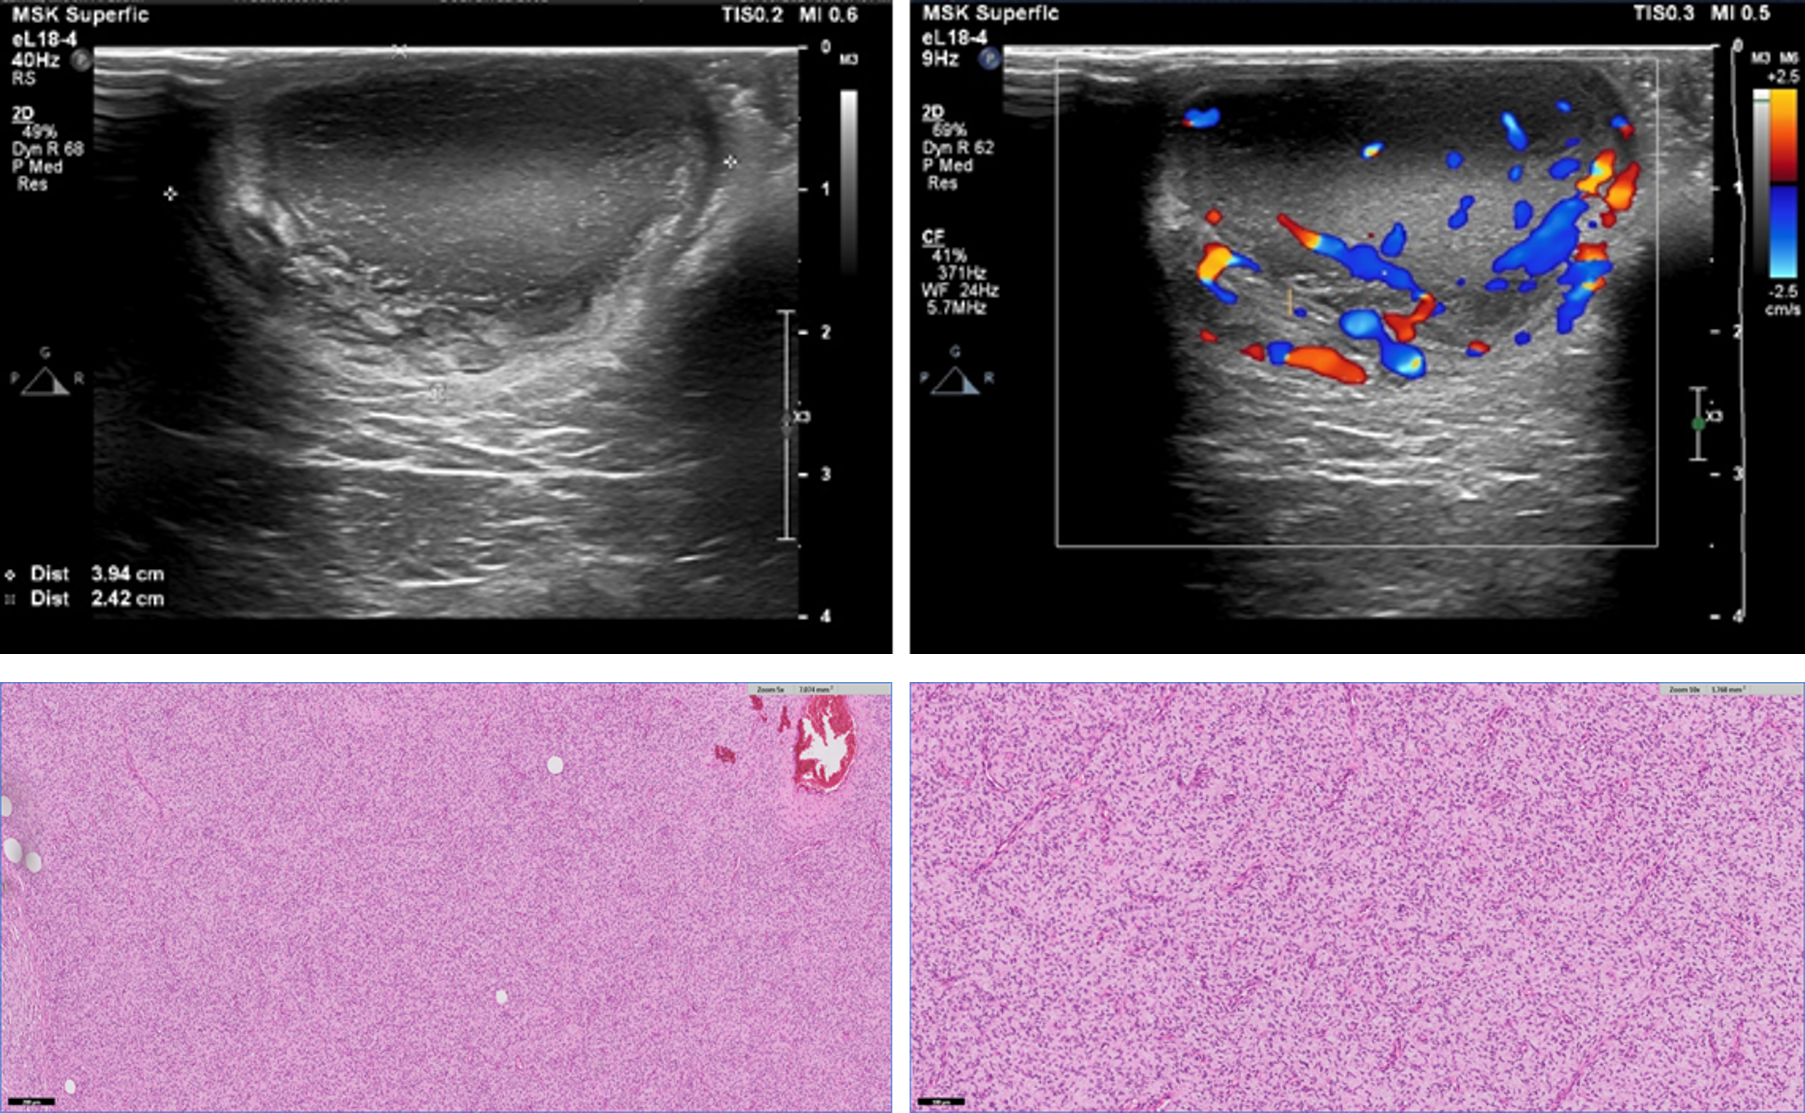

Primary T-Cell Lymphoma of the Prostate in a Dog – Case Report

Marina Laudares Costa, Carlos Eduardo Fonseca-Alves, Gustavo Garkalns de Souza Oliveira, Ana Paula Massae Nakage-Canesin, Paula Christine Bonadio Rezende, Thiago Demarchi Munhoz

bjcr23